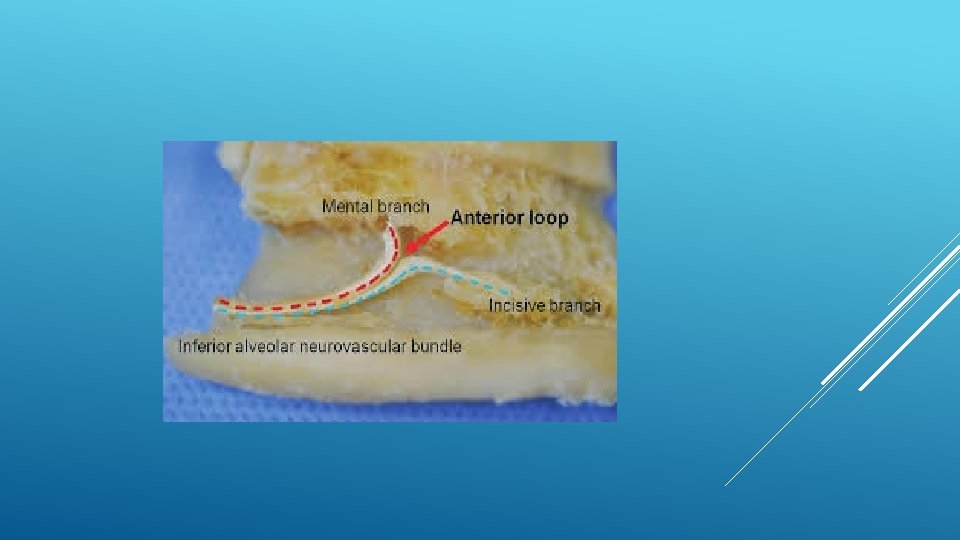

LOCATION AND DIMENSIONS OF THE MENTAL FORAMEN: A RADIOGRAPHIC ANALYSIS BY USING CONE-BEAM COMPUTED TOMOGRAPHY The majority of MF (56%) were located apically between the 2 premolars, and another 35. 7% of MF were positioned below the second premolar. On average, the MF was localized 5. 0 mm from the closest root of the adjacent tooth (range, 0. 3 -9. 8 mm). The mean size of the MF showed a height of 3. 0 mm and a length of 3. 2 mm; however, individual cases showed large differences in height (1. 8 -5. 1 mm) and in length (1. 8 -5. 5 mm). All mental canals exiting the MF demonstrated an upward course in the coronal plane, with 70. 1% of the mental canal presenting an anterior loop (AL) in the axial view. The mean extension of AL in cases with an AL was 2. 3 mm.

THE MENTAL FORAMEN OR "THE CROSSROADS OF THE MANDIBLE. " AN ANATOMIC AND CLINICAL OBSERVATION] [ARTICLE IN FRENCH, GERMAN] THOMAS VON ARX 1 This paper presents a clinical and anatomical review of the mental foramen (MF) based on recent publications (since 1990). Usually, the MF is located below the 2 nd premolar or between the two premolars, but it may also be positioned below the 1 st premolar or below the mesial root of the 1 st molar. At the level of the MF, lingual canals may join the mandibular canal (hence the term "crossroads"). Accessory MF are frequently described in the literature with large ethnic variations in incidence. The emergence pattern of the mental canal usually has an upward and posterior direction. The presence and extent of an "anterior loop" of the mental canal may be overestimated with panoramic radiography. Limited cone-beam computed tomography currently appears to be the most precise radiographic technique for assessment of the "anterior loop". The mental nerve exiting the MF usually has three to four branches for innervation of the soft tissues of the chin, lower lip, facial gingiva and mucosa in the anterior mandible. The clinician is advised to observe a safety distance when performing incisions and osteotomies in the vicinity of the MF.

ANATOMICAL RELATIONSHIP BETWEEN MENTAL FORAMEN, MANDIBULAR TEETH AND RISK OF NERVE INJURY WITH ENDODONTIC TREATMENT he root apex of the mandibular second premolar (70 %), followed by the first premolar (18 %) and then the first molar (12 %), was the closest to the MF. Ninetysix percent of root apices evaluated were >3 mm from the MF. An AL was present in 88 % of the cases. Conclusions: With regards to endodontic treatment, the risk of nerve injury in the vicinity of the MF would appear to be low. However, the high incidence of the AL highlights the need for clinicians to be aware and careful of this important anatomical feature.